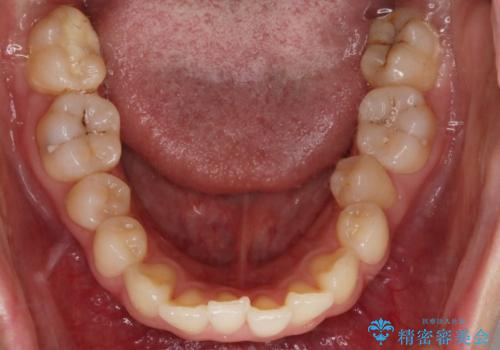

- 笑った時の歯の見え方を治したいとのことで矯正相談にいらっしゃいました。

一見そこまで大きなガタつきはないようにも見えますが、前歯の角度の不揃いや噛み合わせのズレなどから見え方に影響が出てしまっていました。

抜歯は全く必要のないレベルのガタつきだったため、マイクロインプラントを用いて歯全体を後方に移動させていくことできれいな歯並びを獲得することができました。